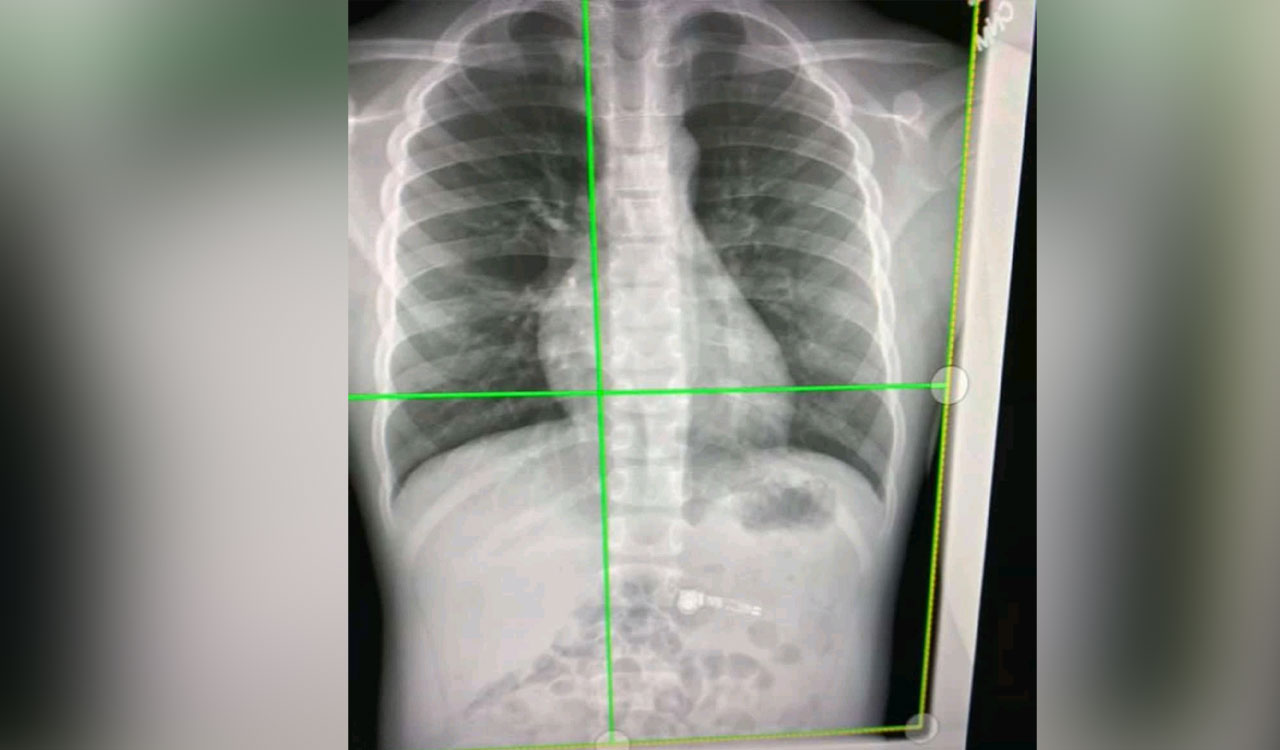

Researchers detect long-Covid’s impact via simple chest X-rays

New York: For patients dealing with lingering respiratory symptoms from the coronavirus, a simple chest X-ray can now reveal its impact on the lungs.

The two-dimensional (2D) scans simply can’t distinguish compromised lung function and a more expensive CT scan is necessary.

In a new study, researchers at the University of Iowa have developed what is called a contrastive learning model.

This model “learns” from composite 2D images constructed from 3D CT images to detect compromised lung function in long-Covid patients.

Another technique, called transfer learning, then conveys lung diagnostic information from a CT scan to a chest X-ray, thus allowing chest X-ray equipment to detect abnormalities the same as if those patients had used a CT scan.